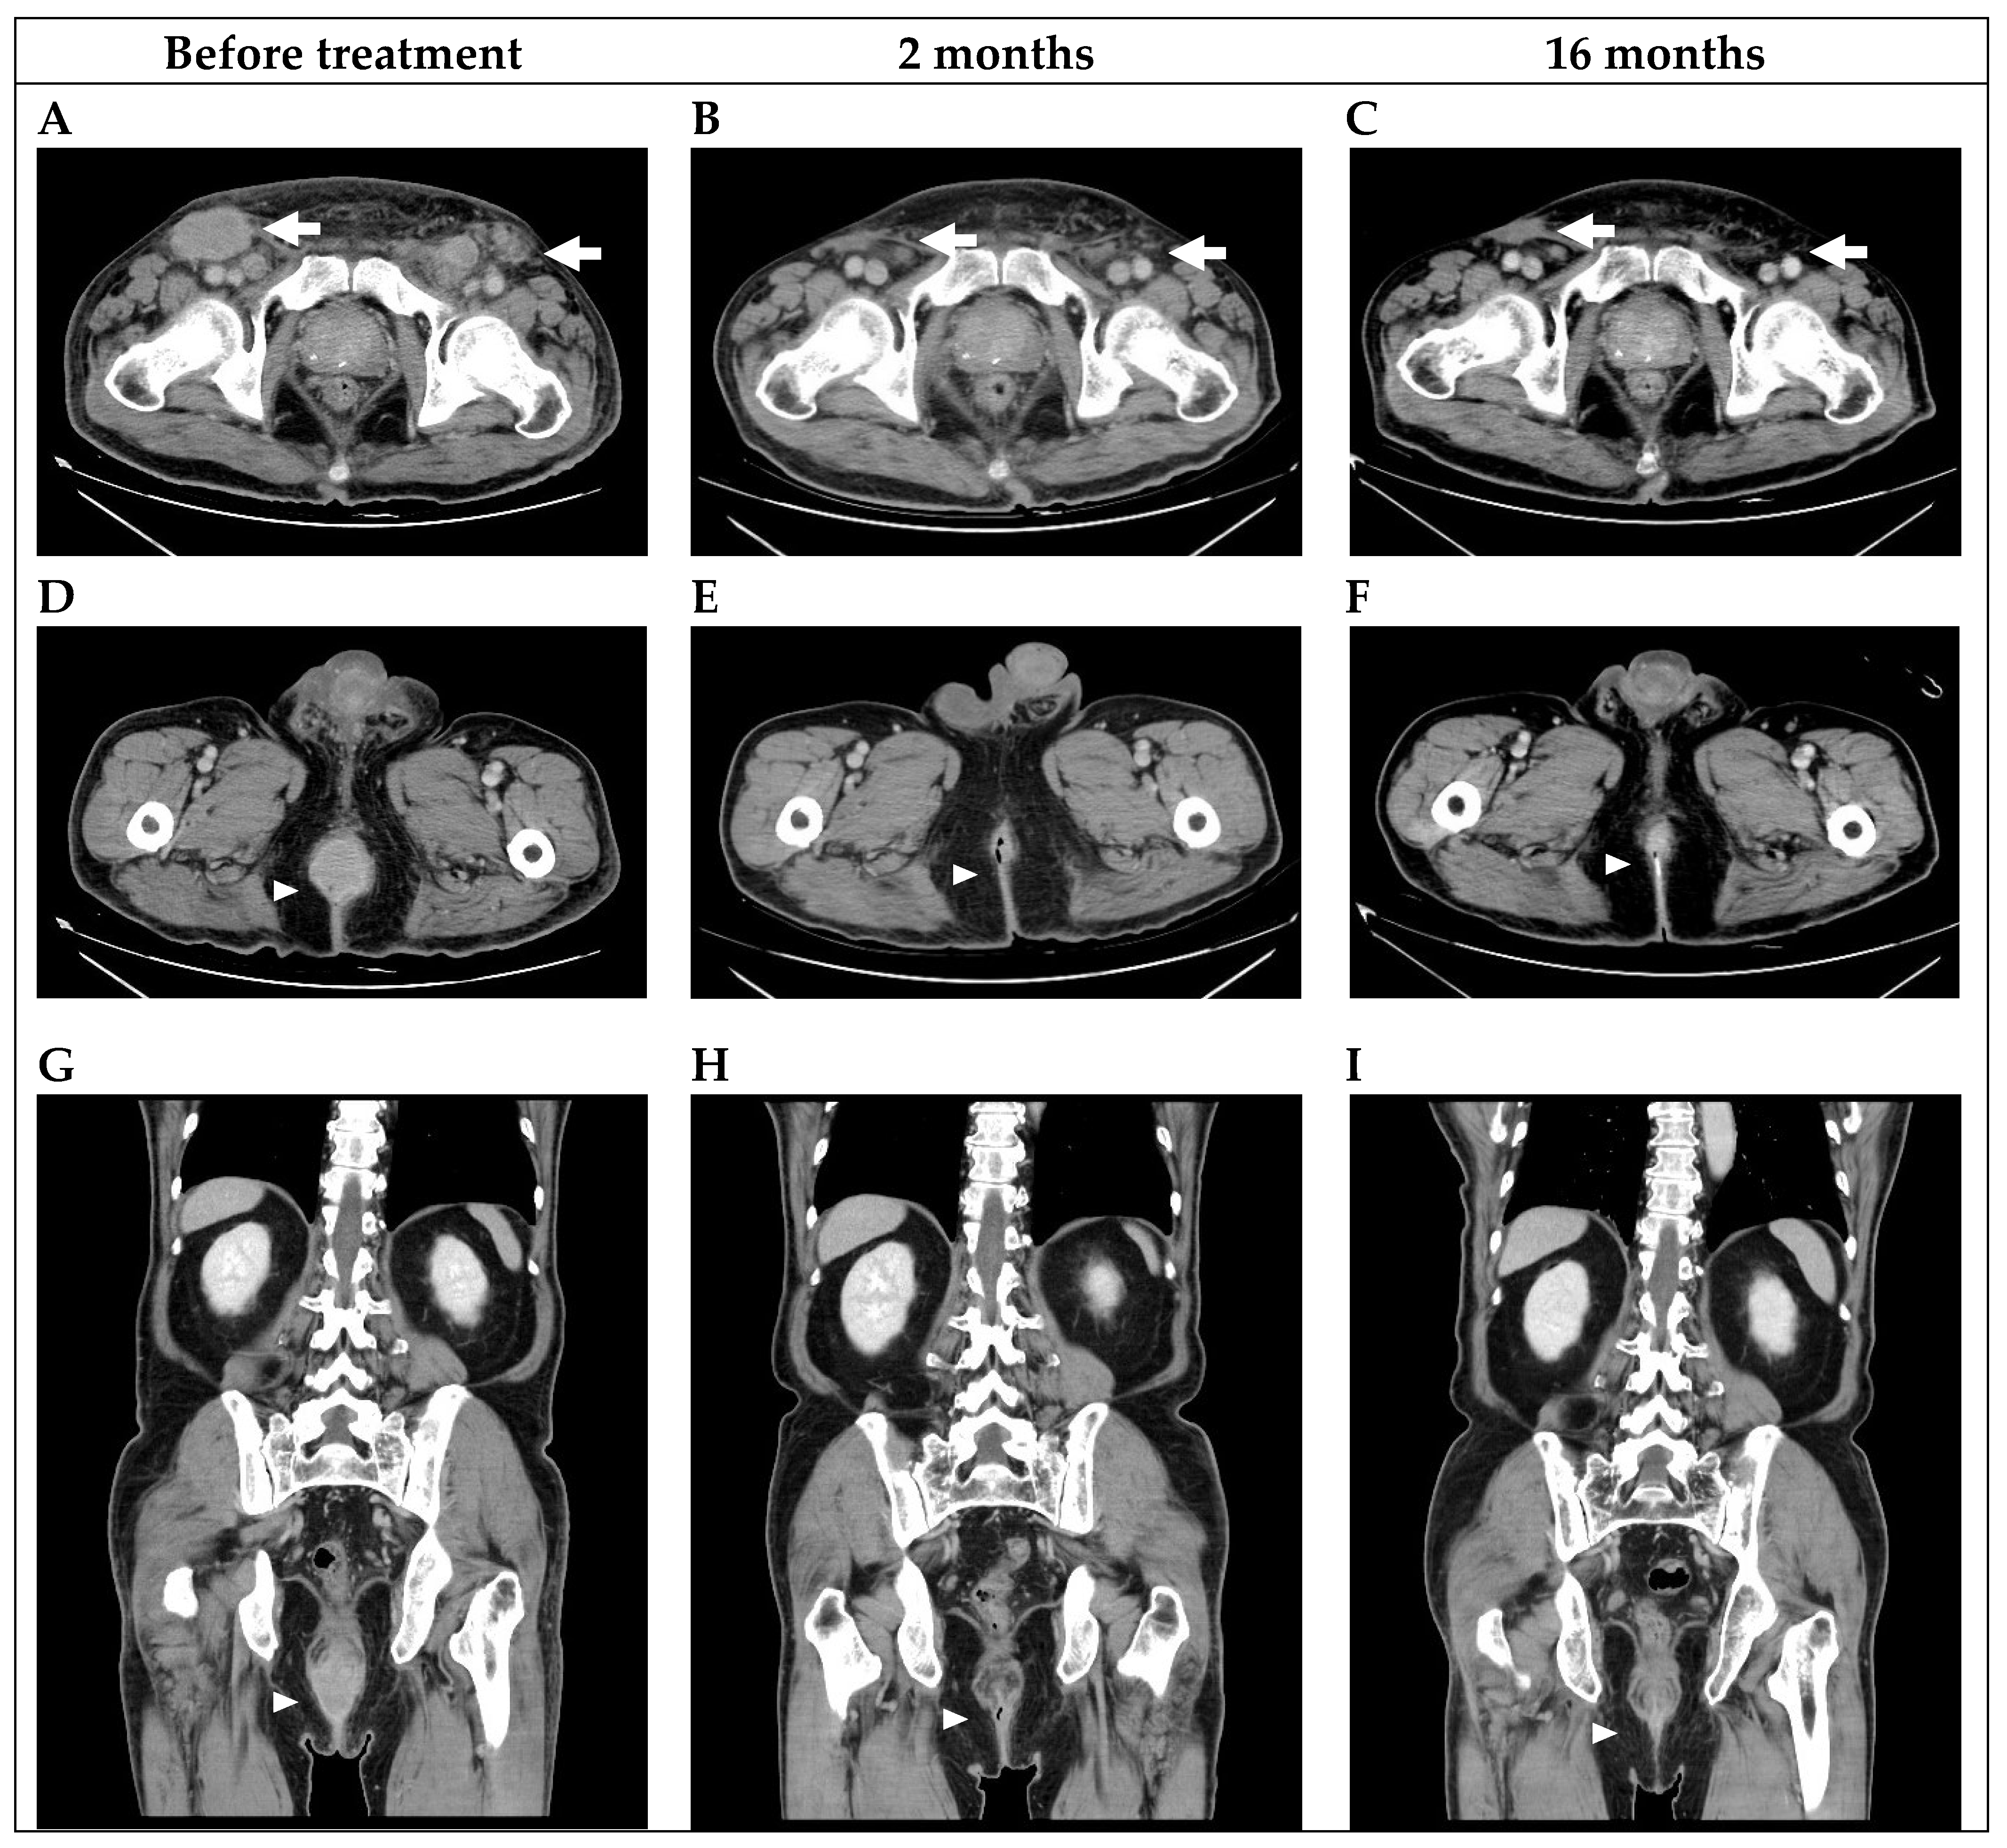

2. Case Presentation